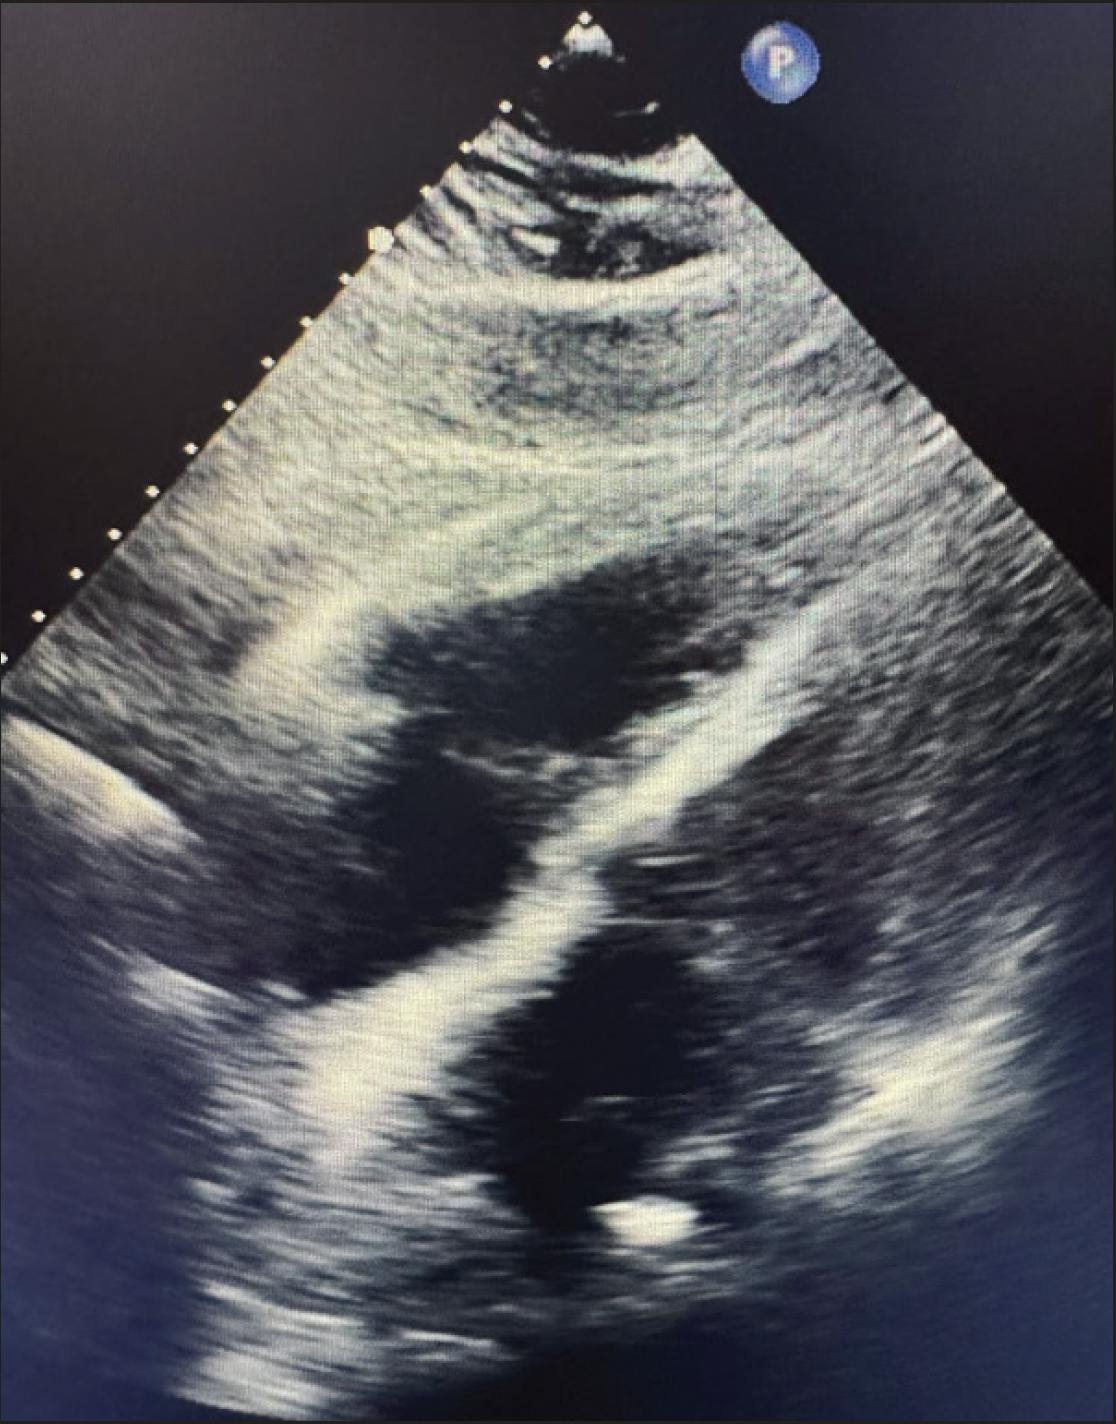

A female patient in her late 60s presented to the emergency department after experiencing a syncopal episode in her car. She reported mild shortness of breath but denied chest pain. Her medical history was notable for a prior postoperative blood clot, for which she was treated with warfarin. Initial vital signs showed a blood pressure of 142/92 mm Hg, a heart rate of 107 bpm, and an oxygen saturation of 95% on room air. Imaging demonstrated right heart strain with an RV/LV ratio of 1.6 and a saddle PE with moderate to large clot burden in the central PAs (Figure 1 and Figure 2). Using a pulmonary wedge pressure catheter, initial PA pressures (PAPs) were 71/26 mm Hg (mean, 45 mm Hg).

Figure 1. Preprocedural CT scan.